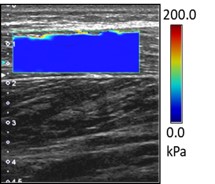

②最先端の技術であるせん断波エラストグラフィー機能で筋の硬さを評価した点.

研究で使用した超音波画像診断装置の画像の一つです.この機能で筋に伝わるせん断波の速度から筋の硬さである弾性率を算出し,その弾性率を指標としてストレッチングの効果を検討しました.